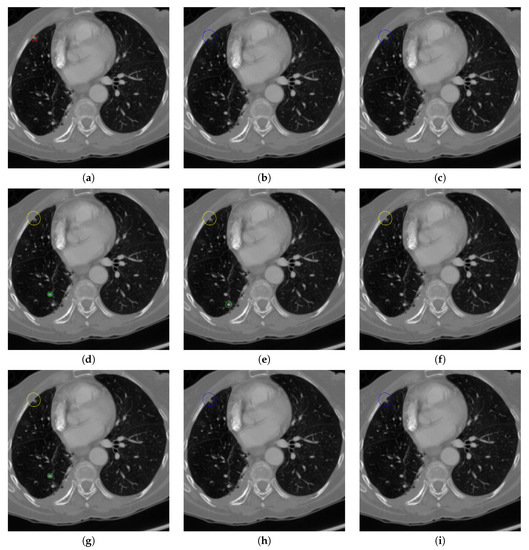

Figure 17 and Figure 18 illustrates the performance of pulmonary nodule detection by different methods on two example images in the LUNA16 dataset. In addition, Figure 19 and Figure 20 illustrates the performance of pulmonary nodule detection by different methods on two examples images in the TianChi dataset. As marked by green circles in Figure 18b,c and Figure 19c, the 3D-FCN and MR-CNN directly detected the nodule candidates from the original CT image without pre-processing, resulting in the incorrect determination of non-nodule tissue outside lung as nodule since the outside-lung organs are not filtered out from the nodule candidates. The 3D-UNET and PRN-HSN add the lung parenchyma region segmentation stage before detecting the nodule candidates inside-lung, so they provide better performance than 3D-FCN and MR-CNN in decreasing the over-estimation rate. However, they still suffer from unsatisfactory results for the following reasons: (1) the lung parenchyma segmentation is generated by simple thresholding with morphological operations so the near-edge regions are lost, shown as the one marked by yellow circle in Figure 20d,e; (2) the convolution kernel used in nodule candidate detection of 3D-UNET is with a small receptive field to learn global features from the image, so it is likely to confuse some small tissues as true nodules with small sizes, shown as the one marked by green circle in Figure 18d and Figure 20d; and (3) the proposed hierarchical saliency network (HSN) in PRN-HSN for nodule candidate classification omits the information with different resolutions, resulting in that the small-size nodule within the weakened, low-resolution region cannot be correctly recognized, as shown by the yellow circle in Figure 18e. The DCNN method simply applies the Faster RCNN method to provide good performance with low computational cost, but it may omit the nodules on the parenchymal edge shown as yellow circles in Figure 20f. CLAHE-SVM method adds a contrast-enhancement pre-processing before the nodule detection, leads to better performance on detecting nodules in the low-contrast region. However, it is easily to over-enhance the small-size tissues and over-estimate them as nodules, as shown by the green circles in Figure 19g andFigure 20g. The detection is also implemented over the whole image, so the nodule on the parenchyma edge may be under-estimated show by the yellow circle in Figure 20g. The Mask-RCNN method provides better effects than the above methods because of the good performance of Mask-RCNN in object detection. However, the performance is not stable for the small-size tissues and the irregular-shape nodule, shown by the green circles in Figure 17h and Figure 19h, and the yellow circle in Figure 19h. The proposed method takes the advantage of a series of U-Net-like networks to perform the nodule detection following a “coarse-to-fine” order of inside-lung region detection, nodule candidate detection and nodule determination. The U-Net network is modified by embedding inception structure, replacing the convolution and pooling by dilated convolution, and adapting multi-scale pooling and multi-resolution convolution connection, for different requirements of the three stages, respectively. Moreover, it makes use of the MSE loss, VGG-19-based perceptual loss as the complement of dice loss to optimize the whole framework. Therefore, as shown in Figure 17i, Figure 18i, Figure 19i and Figure 20i, the proposed framework provides superior performance on pulmonary nodule detection with low over-estimation of non-nodule tissues at the same time.

Figure 17. The result of detecting pulmonary nodules by different methods on one example image in LUNA16 dataset. Red circle represents the ground truth region of nodules, blue circles represent the correct estimation of pulmonary nodules, green circles represent the over-detected nodules, while yellow circles denote the nodules being omitted. (ai) are: ground truth nodule in the given chest CT image, nodule detected by 3D-FCN, MR-CNN, 3D-UNET, PRN-HSN, DCNN, CLAHE-SVM, MASK-RCNN and our proposed method.